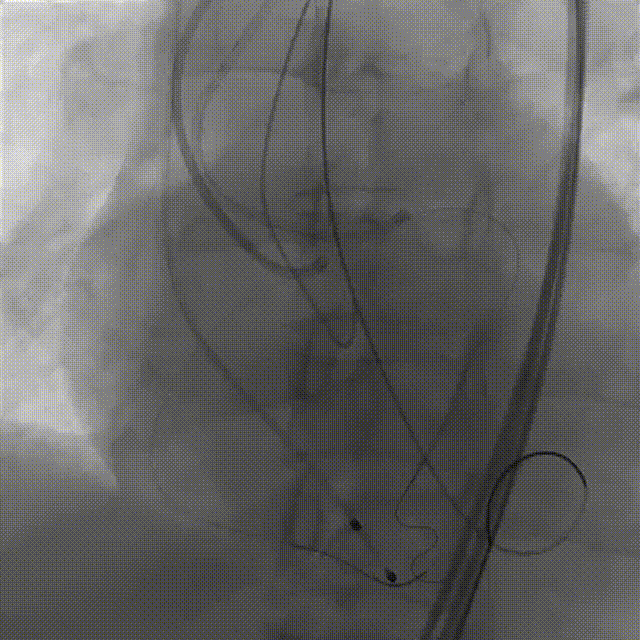

手术过程概览

1.主动脉根部造影

2.18mm球囊预扩

3.左冠造影

4.左冠行支架保护

5.右冠行支架保护

6.右冠造影

7.输送器过弓

8.瓣膜定位

9. 工作位评估冠脉

10.右冠行烟囱支架技术

11.左冠造影评估灌注正常,

撤出支架

12.术后造影